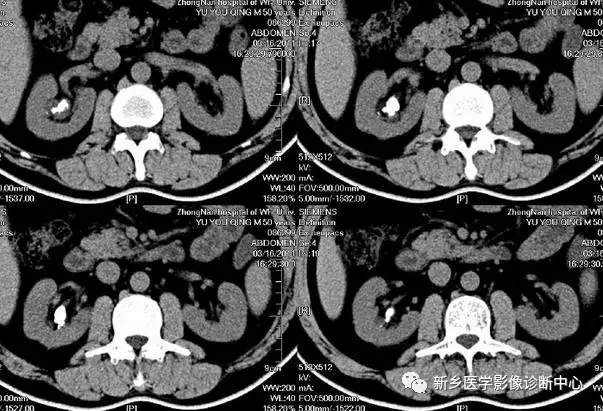

13 肠梗阻

文章图片

1.肠梗阻:中腹部多发阶梯状 , 马蹄状液平 。 2.空肠不全性梗阻 。

1.空肠不全性梗阻:空肠扩展呈弹簧状 。 2.空肠机械性梗阻:弹簧征